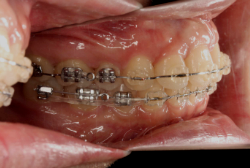

成長発育期の上顎前突症例・非抜歯治療

診断の結果、典型的なアングル2級1類の上顎前突です。上下歯列の正中の不一致も見られます。しかし、歯の大きさは平均値に近く、配列の凸凹がそれほど見られません。このまま放置すると、将来的には抜歯を伴う矯正治療を行う可能性が高くなりますが、このタイミングで適切な治療をすると、非抜歯治療が可能かもしれません。

矯正歯科医が着目するのは、奥歯の噛み合わせの位置関係です。前歯の位置にそれなりの差が生じていても、奥歯の位置が正しければそれほど重症という評価にはなりません。このケースの場合は、上下の第一大臼歯の位置関係は、直線的に一致しているタイプでした(矢印が一致)。混合歯列時期の奥歯の位置関係としては、ほぼ正常な状態といえますが、症状から言うと、上の奥歯をもっと後ろに下げてやることができれば、上顎歯列全体に余裕ができるので、凸凹も解消できるし、前歯の傾きを内向きに修正することもできると考えられました。しかしこのまま全体に永久歯が生えきってしまうと、上の前歯が出たままになってしまいますので、生え替わりが完了する前に大急ぎで奥歯を後ろに下げる必要があると判断しました。

こういう症状でもっとも効果があるのが、顎外固定装置と言って、お口の外部から奥歯に力をかける方法です。 写真の装置はネックバンドというタイプの装置です。この装置は取り外し式ですので、夜寝るときに毎日自分で取り付けて、寝ている間に少しずつ上の奥歯を後ろに下げていきます。この装置には、奥歯を後ろに下げる効果だけでなく、上顎の過剰な成長発育の抑制、下顎の成長促進作用があるとされており、上顎前突の症状にはいずれも有利な効果が期待できます。

ネックバンドを1年半使用して、上顎大臼歯が十分後ろに下がったところで、裏側にリンガルアーチという固定のワイヤーを取り付けて、新しく生じた隙間が狭くならないよう「保隙(ほげき)」という処置をして、永久歯が生えそろうまで待機中の様子です。配列全体に隙間が生じているのがお分かりいただけると思います。これだけの隙間が確保できていれば、抜歯をしなくても、あとで上の前歯を内側に理想的な角度で引っ込めることができます。このように完全に永久歯列になる前に、十分な隙間が確保できるかどうかが、非抜歯で矯正できるかどうかの分かれ目になります。

初診時と違い、上の奥歯がより後方に下がっていることが分かります。ただしこの段階では奥歯は後ろに下がりすぎの状態です。しかし次の段階でマルチブラケット法を始めると、上の奥歯は次第に前にズレて来ます。最終段階で正しい位置にするためには、この段階では余分に後ろに下がっている必要があります。

第2段階としてマルチブラケット法を非抜歯で1年間行いました。歯の傾斜が修正され、正中も一致し、美しく機能的な配列に仕上がりました。再診時に確保した隙間をすべて使って、すべての永久歯を理想的な位置に配列することができました。前傾していた上の前歯は真っ直ぐに直立し、完全な正常咬合が確立できています。